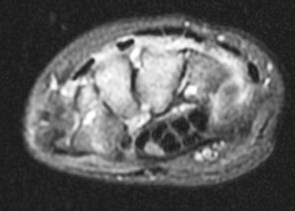

14 y/o with history of bilateral wrist pain.

His carries a known diagnosis of Juvenile Rheumatoid Arthritis. (RID3610) New term is JIA. He has failed steroid therapy and methotrexate. Currently on humira. R/O osseous change. Its ruled in. Reference article.

Juvenile idiopathic arthritis